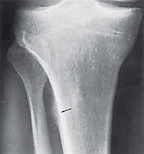

Fig. 2: Popliteal groove.

The AP tunnel view demonstrates an accentuated groove (Fig. 2, white arrow) for the patellar tendon, which is a normal finding and should not be confused with erosion. The popliteus muscle origin is on the anterior portion of the popliteal groove on the lateral femoral condyle; a lesser origin is from the head of the fibula, and there is an additional origin from the lateral meniscus in a small percent of the population (Fig. 3). It courses under the lateral collateral ligament, descends into the popliteus hiatus, then passes under the arcuate ligament and becomes extra-articular before finally joining its muscle belly. It's insertion is fan-like on the posterior surface of the tibia above the popliteal line.